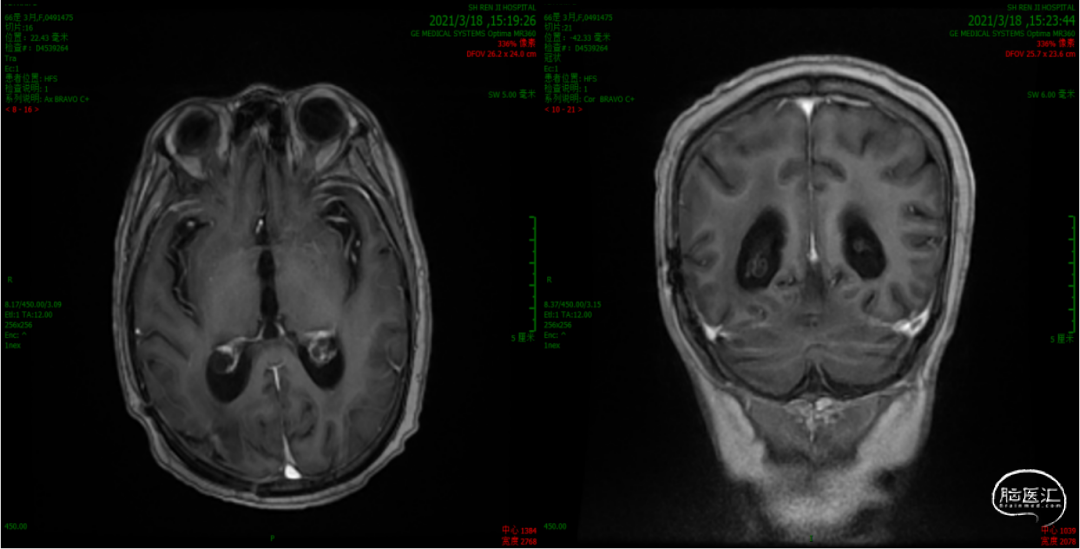

3. 2021年3月18日,2021年3月起,患者诉左侧肢体乏力,需搀扶行走。影像学检查显示,右侧脑室后角旁见结节样环形强化灶,直径7-8mm。MRS:NAA峰可见下降,Cho峰升高。Cho/Cr为0.748,Cho/NAA为2.13,考虑肿瘤复发可能。患者行射波刀治疗(24Gy/4FX),TMZ+安罗替尼2周期,TTFields重新定位,电场治疗调整贴片位置。